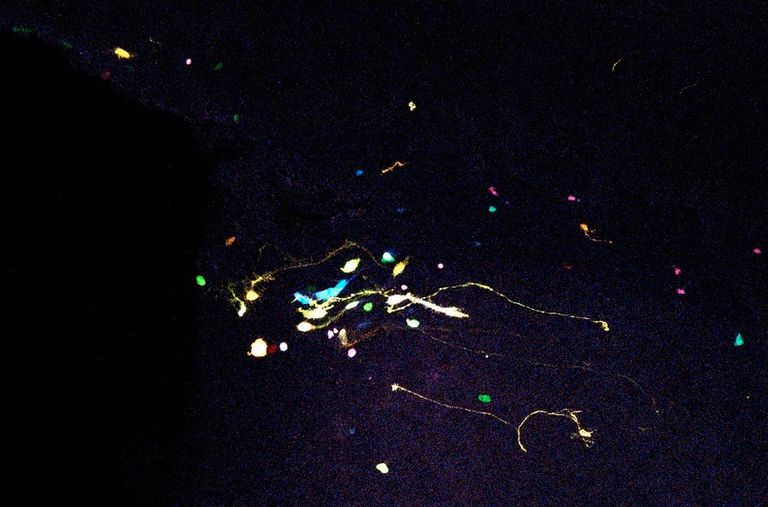

وأضافت: "حددت هذه الدراسة مجموعة من الأساليب التي تسمح بتصور نشأة خلايا عصبية جديدة في (التلفيف المسنن) لدى الإنسان البالغ، وهو ما سمح، للمرة الأولى، بمعرفة بيانات غير مسبوقة عن مراحل النضج المختلفة التي تمر بها الخلايا العصبية الجديدة في هذه المنطقة من الدماغ".

وتستند هذه "المجموعة من الأساليب" إلى دراسة عينات من أنسجة الدماغ البشرية، من خلال علاجات كيميائية مختلفة.

وتوضح يورنس مارتين أن الطريقة التي تُعالج بها أنسجة الدماغ تؤثر على اكتشاف الخلايا العصبية غير الناضجة في الحُصين البشري.